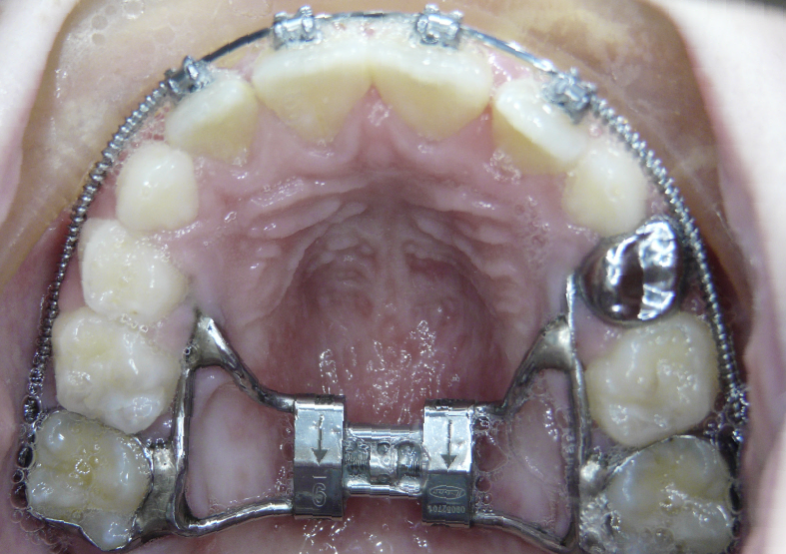

Posterior Crossbite

Top teeth are inside of bottom teeth.